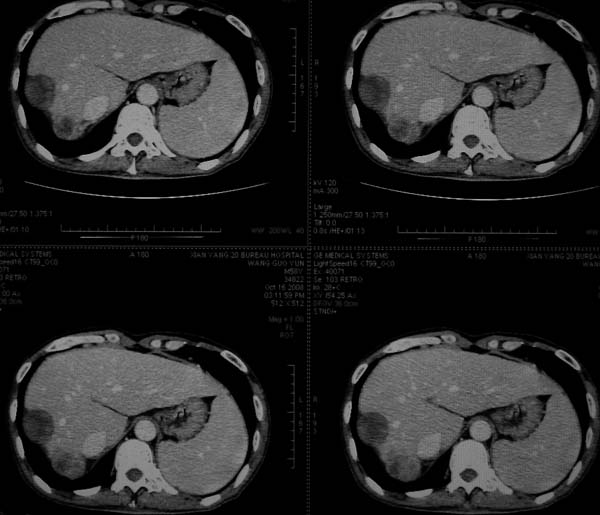

标题: CT16292:男,53岁,上腹部不适2月,B超发现肝内占位病变。 [打印本页]

标题: CT16292:男,53岁,上腹部不适2月,B超发现肝内占位病变。

符合肝ca增强,\"快进快出\";肝叶比例失常,右叶萎缩,肝裂增宽,脾大,肝硬化可能.

支持结节型肝癌。肝硬化脾大,病人是不是做过手术。

肝脏体积变小,肝裂增宽,分布异常,肝尾叶增大,脾肿大,考虑肝硬化可能性大,右肝病灶呈现早期充盈,延迟强化考虑肝内胆管细胞癌可能,不除外血管瘤

肝硬、脾大,右肾在稍息,考虑结节型肝癌可能,不排除血管瘤。

支持 结节型肝癌;肝硬化、脾大。

肝硬化,多结节肝癌。比较典型的表现了。

肝叶比例失调,左叶增大,肝裂增宽,脾脏增大,门脉增宽,肝右叶包膜下多发结节样阴影,增强虽说强化幅度不大,但还是符合快进快出特点;考虑肝硬化、脾大、结节型肝癌。胆管细胞癌多有延时强化、肝包膜凹陷征、周围胆管扩张等特点,本例明显不符;故不考虑。

支持结节型肝癌 肝硬化 脾大